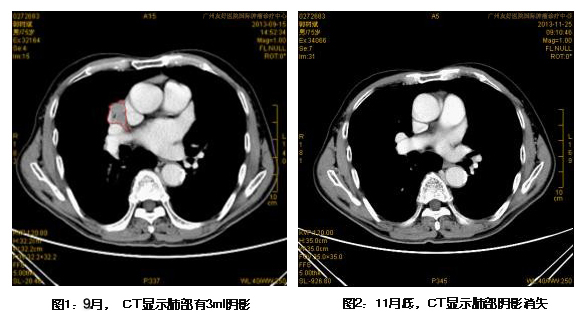

自9月开始,肖先生开始接受一个疗程的WB-1无创全身热疗系统治疗。他说:“治疗时没有感到任何不适,也没有想象中的以为会很烫,躺在床上个把小时,睡个觉醒来,就治疗完了,真的是绿色治疗。”几次热疗后,肖先生的咳嗽、咳痰症状缓解,咳血也止住了,吃饭睡觉都恢复了正常。11月底的CT报告显示,肖先生肺部的肿块完全消失。